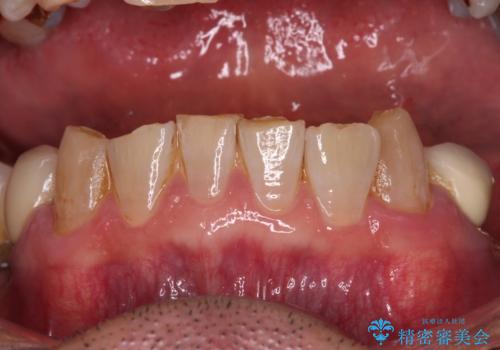

- 下顎両側の欠損と上顎前歯のデコボコを気にして来院された患者様です。

デコボコは今まで気にせずにいたそうですが、奥歯の欠損改善を機に、矯正治療に興味があるので、相談したいとのことでした。

奥歯に欠損が多く、矯正治療はやや難航することが予想されますが、患者様の希望もあり、上顎左右小臼歯を1本ずつ抜歯し、ワイヤー装置にて矯正治療を行うこととしました。